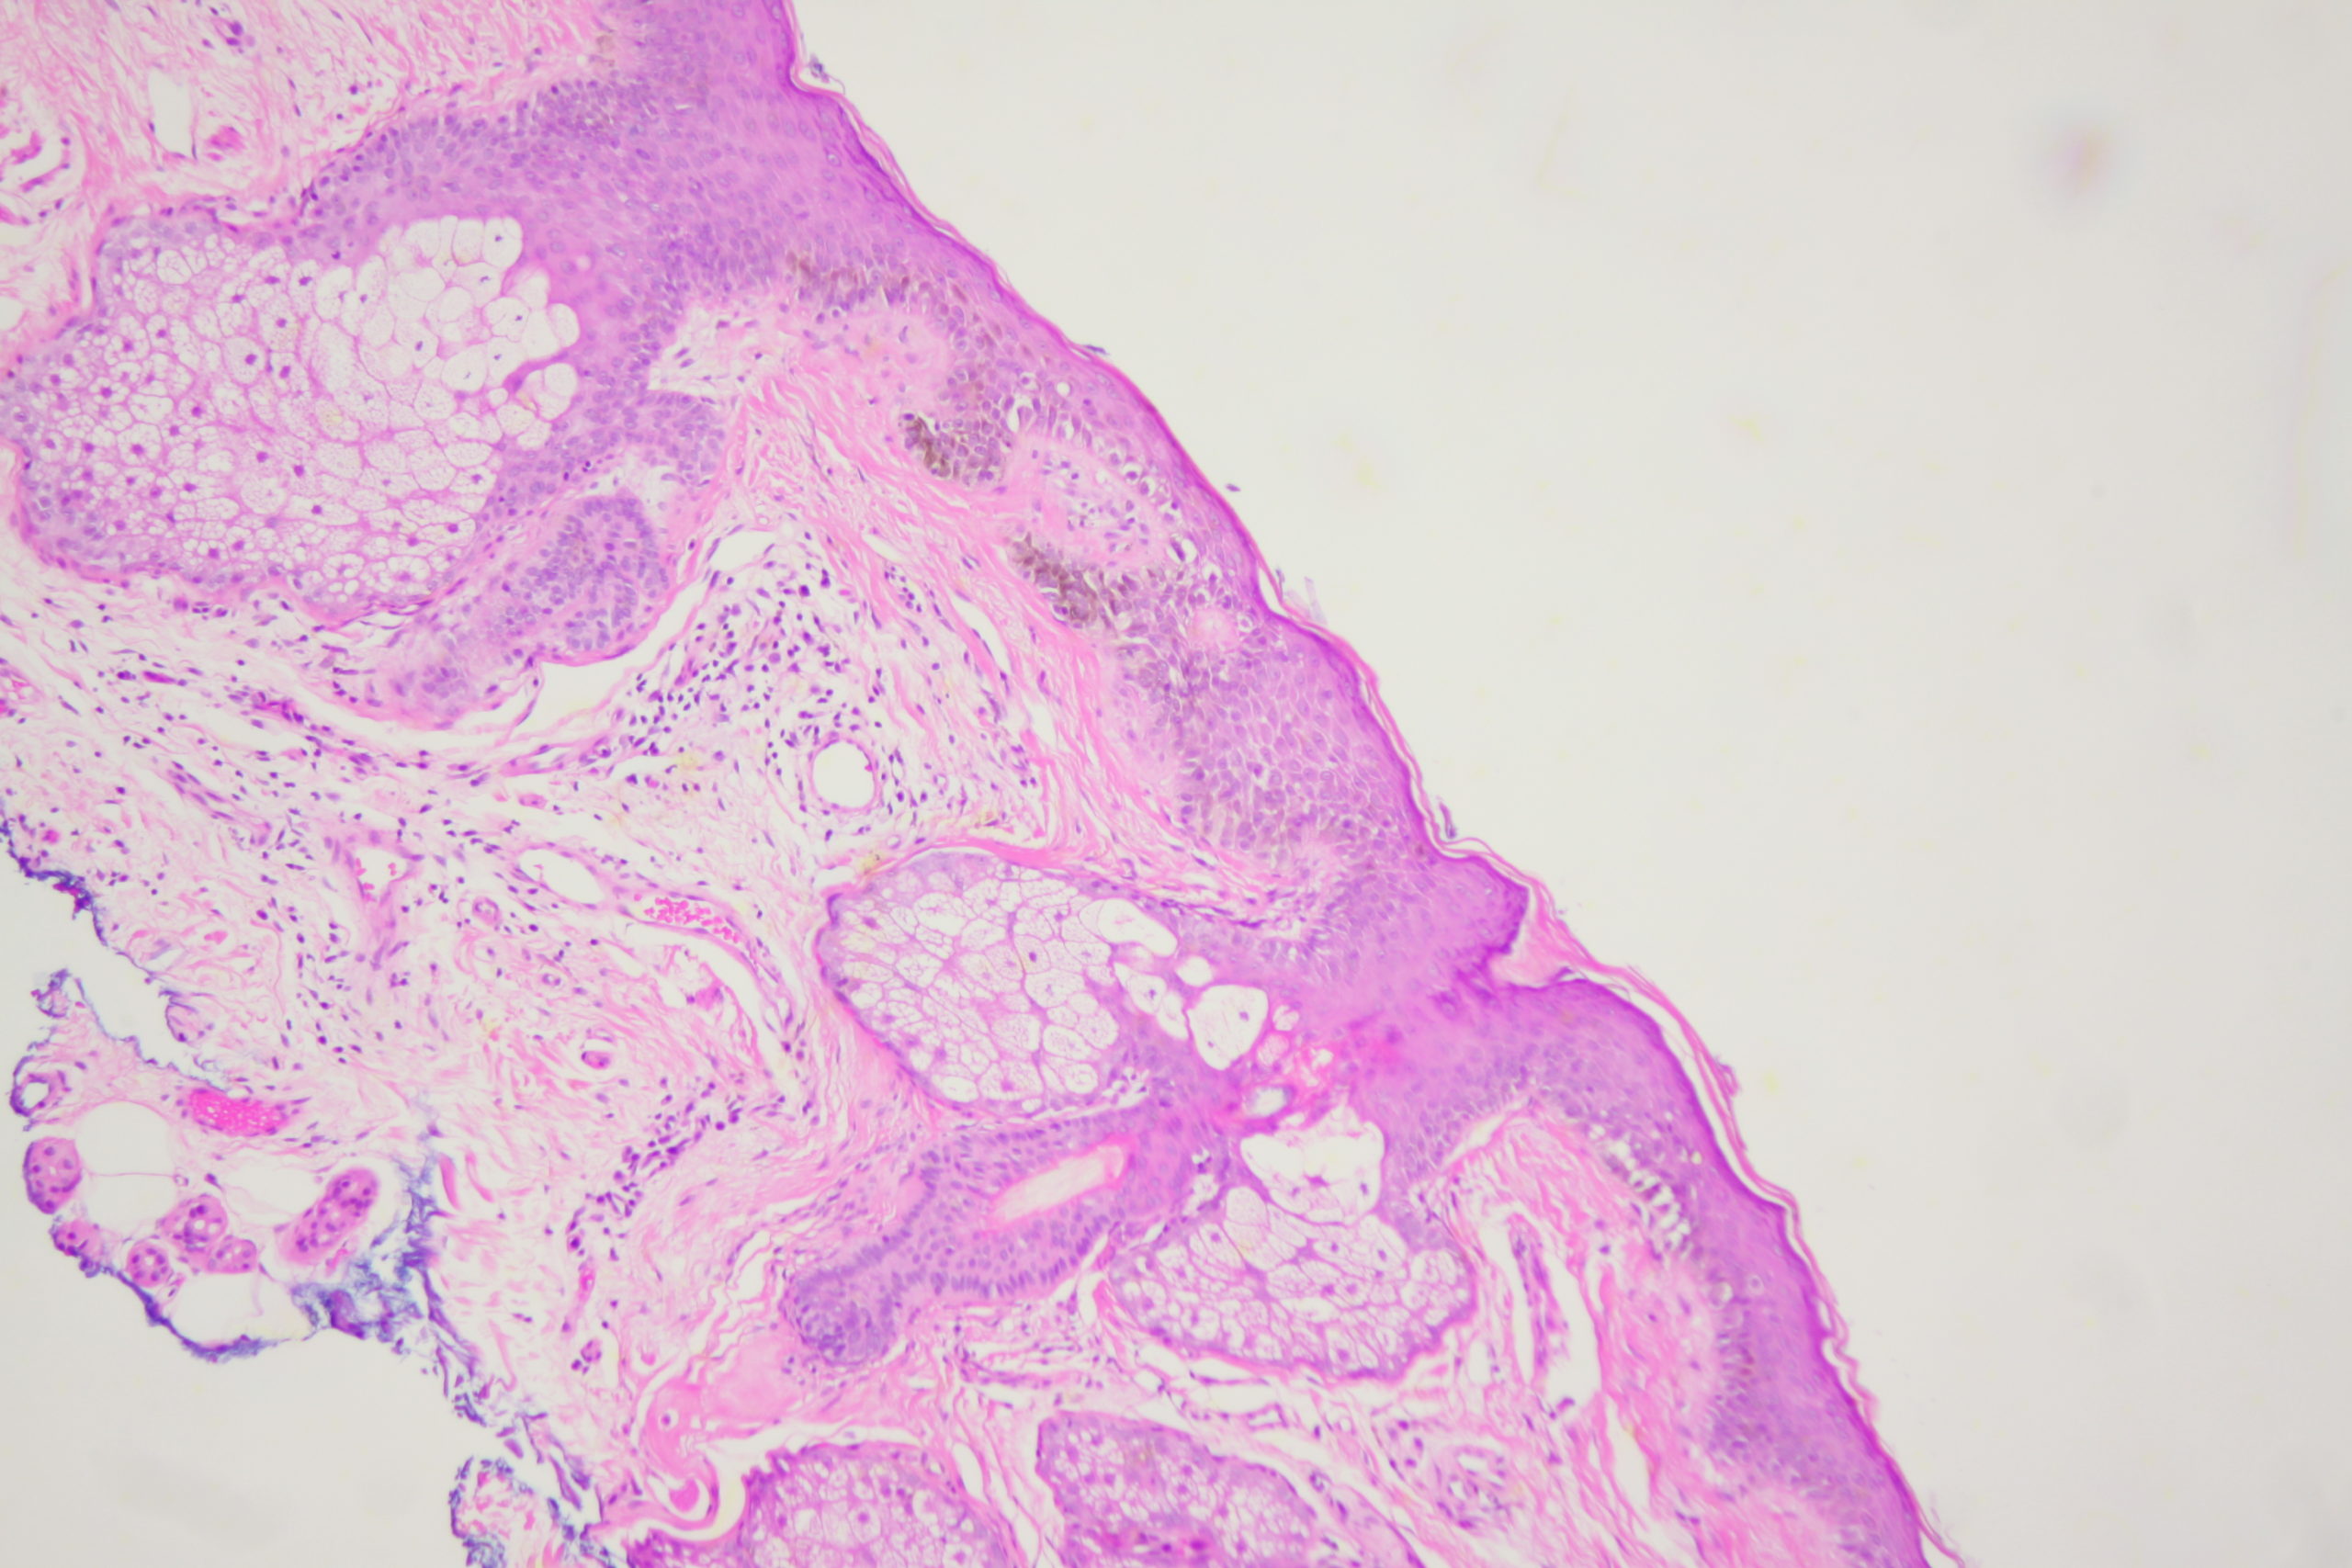

Site: Cheek

Diagnosis: Lentigo Maligna

A pigmented lesion on the cheek that has slowly been increasing in size over several years. Male aged 65. Smooth surface.

Dermatoscopy shows pigment dots and pigment around follicles as grey circles. PRAME and Sox 10 showed atypical melanocytes along the DEJ extending into and down follicles with localised upward pagetoid spread. Early Lentigo maligna / Superficial intraepidermal melanoma.